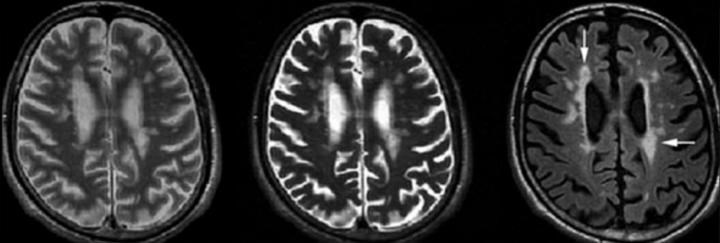

Konvansiyonel T2 lezyonları, aynı zamanda diffüz, büyük ve düzensiz hiperintens alanları da kapsar; bu görünüme “kirli ak madde” adı verilir. Bunlar sınırları belirsiz, özellikle oksipital horn çevresine yerleşen geniş lezyonlardır ve RRMS hastalarının yaklaşık %17’sinde tanımlanır.

- Jukstakortikal lezyonlar

İMG – MRG-5: “Kirli ak madde” görünümü.

İMG – MRG-6: Jukstakortikal lezyonlar.